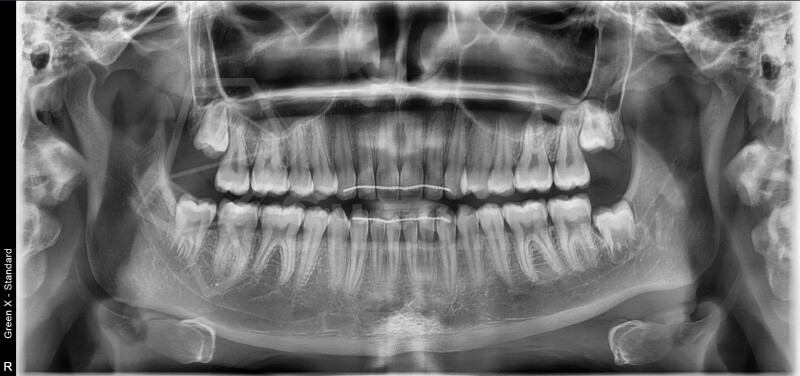

Zdjęcie panoramiczne (pantomogram) obejmuje całe uzębienie i szczęki, pokazując zmiany, których nie widać na zdjęciach punktowych RTG – takie jak torbiele, guzy, stany zapalne czy zwyrodnienia stawów.

Pracownia wyposażona jest w tomograf stożkowy Vatech Green X (model 2025) – najnowszej generacji urządzenie, które łączy najwyższą jakość obrazów 2D i 3D z minimalną dawkąpromieniowania.

Skanowanie trwa zaledwie 2,9 sekundy, a technologia AI automatycznie redukuje zakłócenia i poprawia ostrość zdjęć.